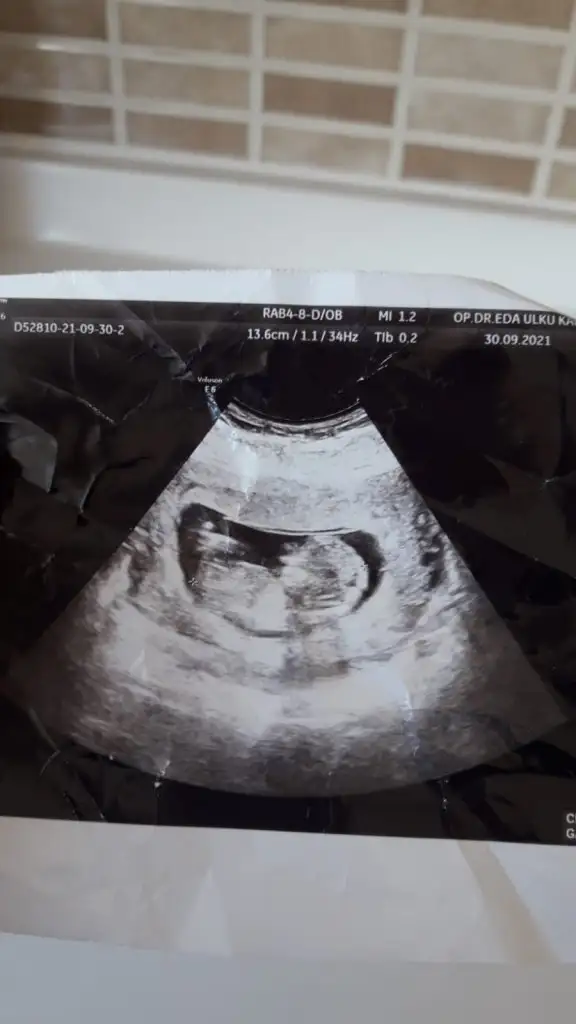

Doktor %70 kiz gibi ama daha erken onumuzdeki ay net belli olur dedi. Fakat prof dr oldugu icin yanilacagini sanmiyorum. Senin dr baya namini duydum sitede. Sen de emin olamamissin o zaman kız mi geliyor acabaEmin olmadım sanki erkek gibi

Kiz gibi görünüyorMerhabaIkra meyra benım tahminime kız demiştiniz tuttu, buda eltimin 13 haftalık sizce bebeğimiz nedir ???

BakalımDoktor %70 kiz gibi ama daha erken onumuzdeki ay net belli olur dedi. Fakat prof dr oldugu icin yanilacagini sanmiyorum. Senin dr baya namini duydum sitede. Sen de emin olamamissin o zaman kız mi geliyor acaba